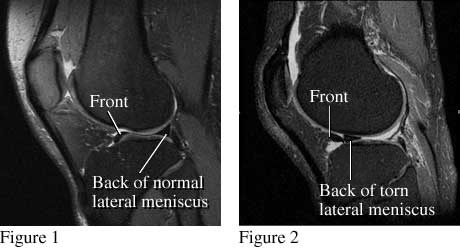

Knee MRI